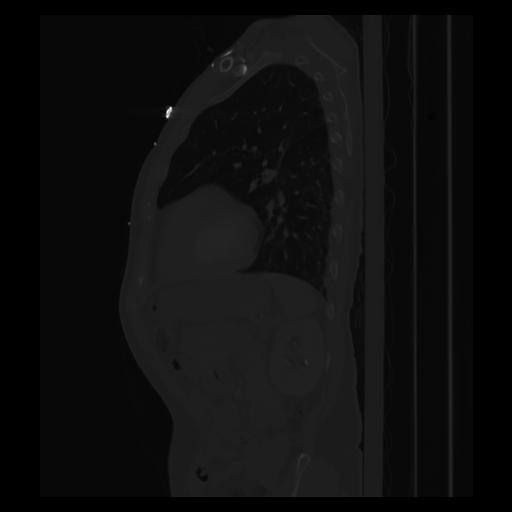

30 CUERPO,CE,Sagittal,3.000,CUERPO,Sagittal,